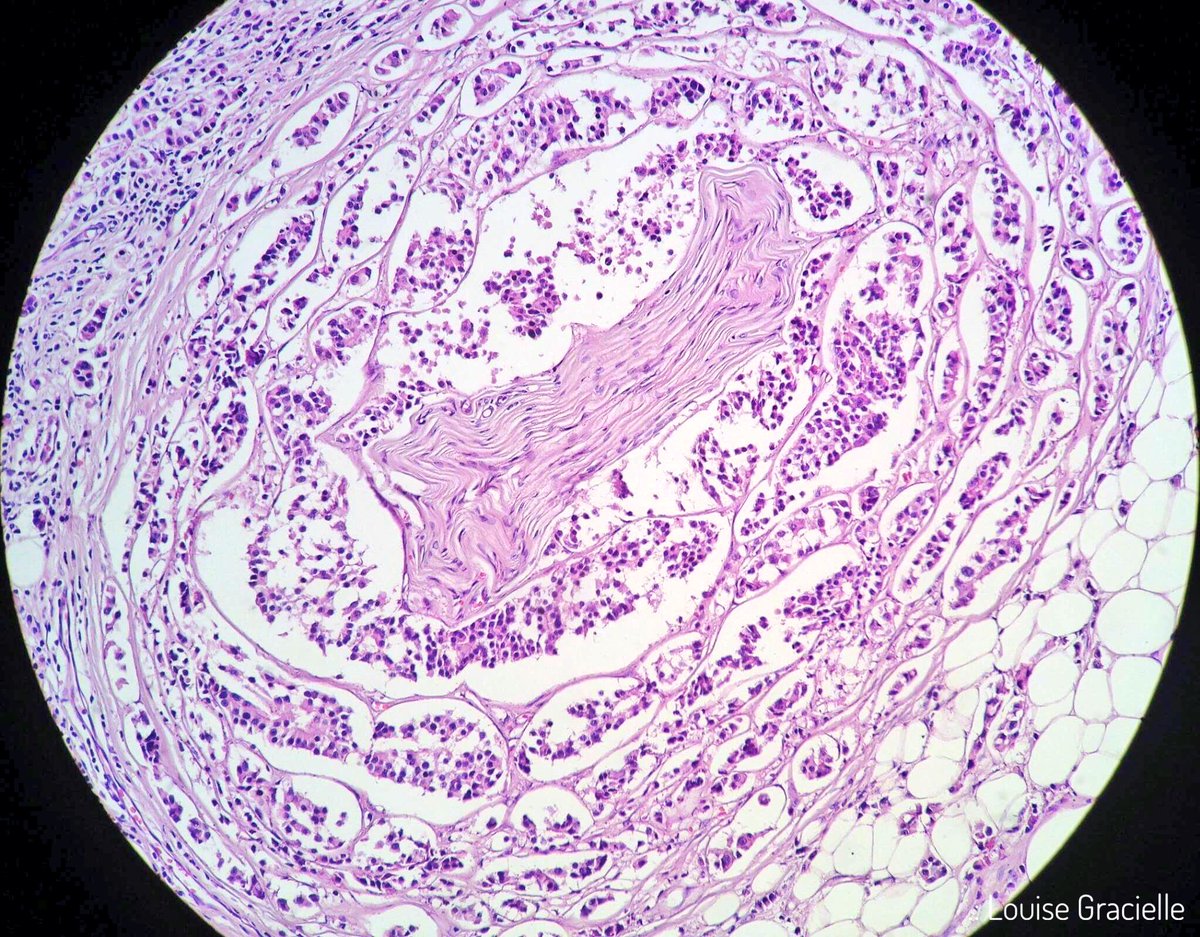

Breast carcinoma infiltrating a Pacinian corpuscle in a male patient. #breastcancer #pathology #paciniancorpuscle #breastpathology

LouiseGracielle's tweet image. Breast carcinoma infiltrating a Pacinian corpuscle in a male patient. #breastcancer #pathology #paciniancorpuscle #breastpathology